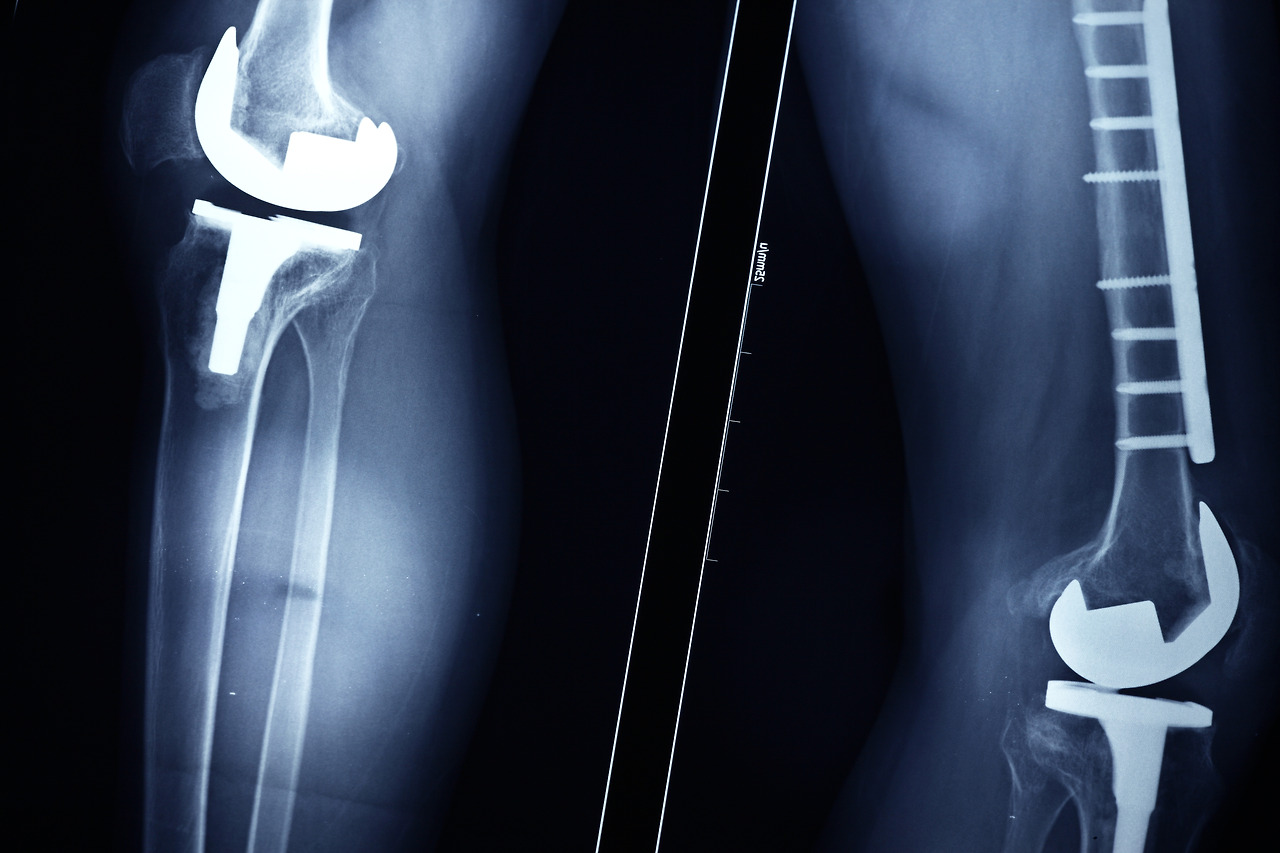

인공관절 클리닉

● 슬관절 담당: 일산백병원 정형외과 나경욱 교수 , 조진호교수

● 고관절 담당: 일산백병원 정형외과 주석규 교수, 오형근교수

● 족관절 담당: 일산백병원 정형외과 서진수 교수

관절의 연골이 파괴 또는 강직 되어 더 이상 관절을 사용할 수 없는 경우, 인공 관절로 새로운 관절을 만들어 주는 수술이다.

인체의 모든 사지 관절 즉 고관절, 슬관절(무릎), 견관절(어깨), 주관절(팔꿈치), 수부관절(손목), 족관절(발목) 등에 인공관절로 대체할 수 있다. 이로인해 원활한 관절운동이 가능하다.

특히 일자적 인공관절 치환술뿐만 아니라, 수명이 다한 인공관절을 바꿔주는 재치환술을 주로 시행하고 있다.